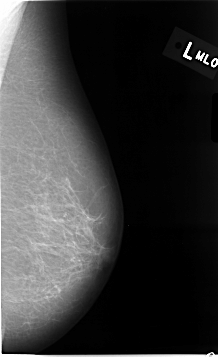

C_0014_1.LEFT_MLO

LEFT_MLO LINES 4632 PIXELS_PER_LINE 2824 BITS_PER_PIXEL 12 RESOLUTION 50 NON_OVERLAY